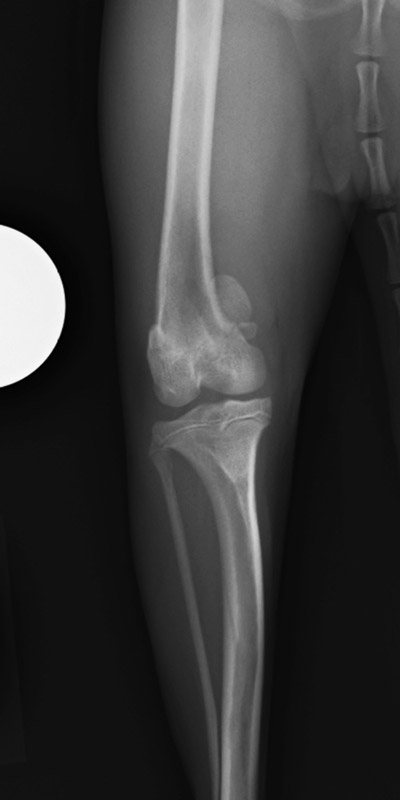

肘関節内骨折

アメリカン・コッカー・スパニエル(5歳)

車の窓から落下

手術前

手術後